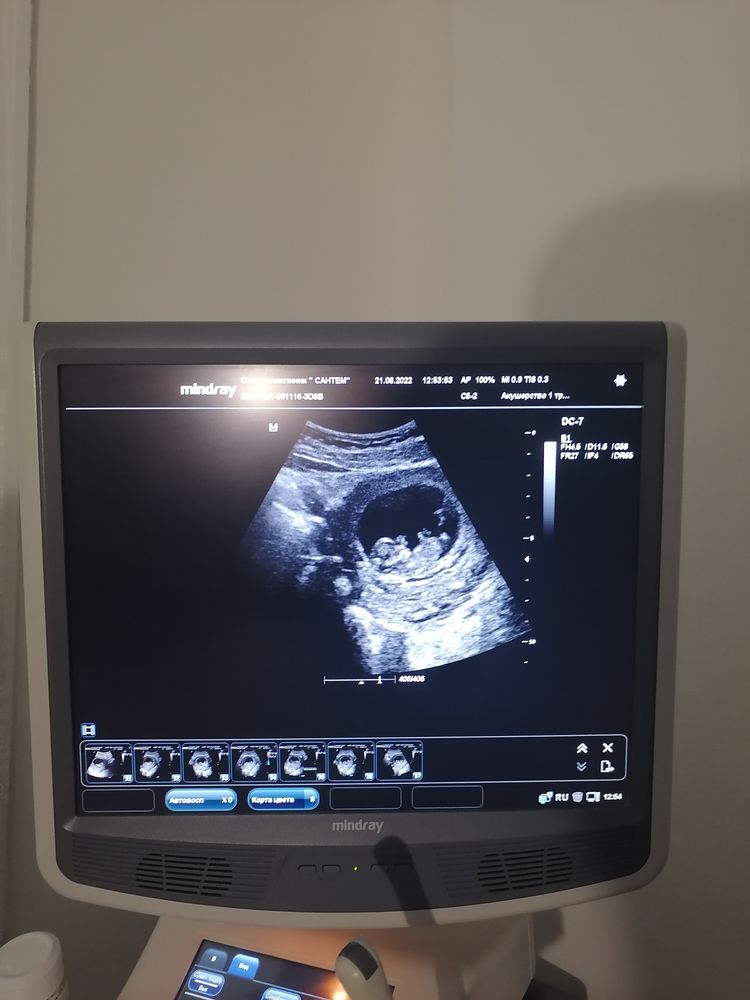

Врач пустил нас вместе, делали и вагинальное и через живот, все посмотрели. Нам малыш показал представление. Так шивелился, что не могли посчитать ктр 😂 у мужа улыбка до ушей ☺️ потом устал от нас, отвернулся и уснул ❤️

Очень рада что сходили вместе и он теперь понимает что внутри меня происходит ☺️😂 узи делали на сроке 10+2, ктр 38. Врач поставила срок 10+5